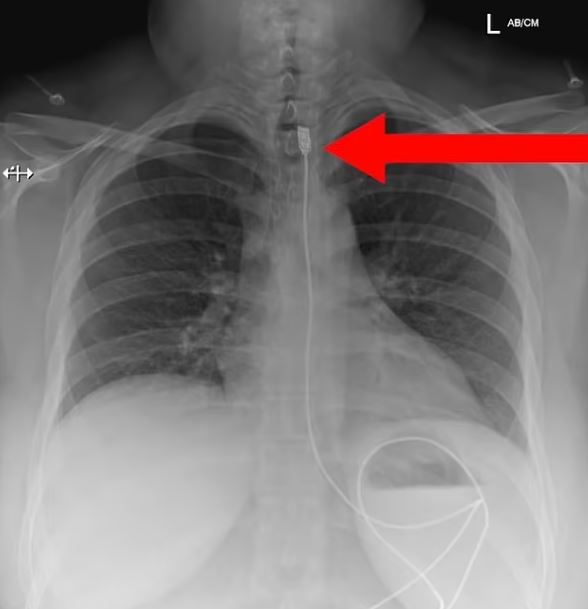

波蘭一名女子因為呼吸困難緊急送醫,照X檢查後,醫生竟然在她體內看到1公尺長的充電線......

根據外媒《Dailymail》的報導,波蘭醫療救援團隊「Gotowi Do Ratowania」收治了一起驚人病例,一名女子因為呼吸困難緊急送醫,她被安排照X光,檢查結果出爐後嚇壞醫生,因為她體內卡了一條長1公尺的iPhone充電線,從喉嚨處一路延伸到腸子裡。

女子這時才坦言,她因為患有「異食癖」,試圖吞下又細又長的充電線,不料充電接頭卡在喉嚨食道處,導致她無法呼吸,只好趕緊求助醫院。女子後來經過手術順利取出充電線,人已經康復出院。